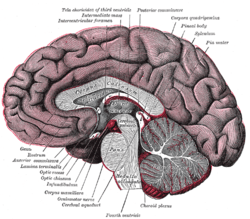

Hind- and mid-brains; posterolateral view Median sagittal section of brain

Median sagittal section of brain Nuclei of the pons and brainstem